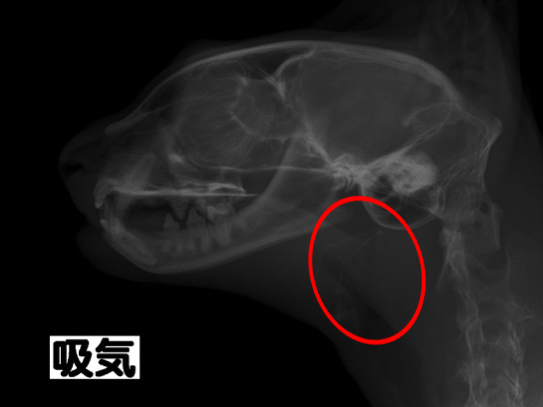

レントゲン検査:赤丸が狭窄部位

約3ヶ月前より鼻炎症状を主訴に他院を受診し、鼻炎としての治療が行われたものの、十分な改善が見られなかったため、精査を目的として当院を受診されました。 当院にてCT検査を実施したところ、鼻咽頭部に顕著な狭窄を認めたことから、呼吸器症状の改善を目的に、鼻咽頭狭窄に対するバルーン拡張術を実施しました。 処置後の経過は良好で、全身状態も安定していたため当日退院としました。 その後も経過観察を継続しており、現在までに7ヶ月が経過しましたが、再発は認められていません。